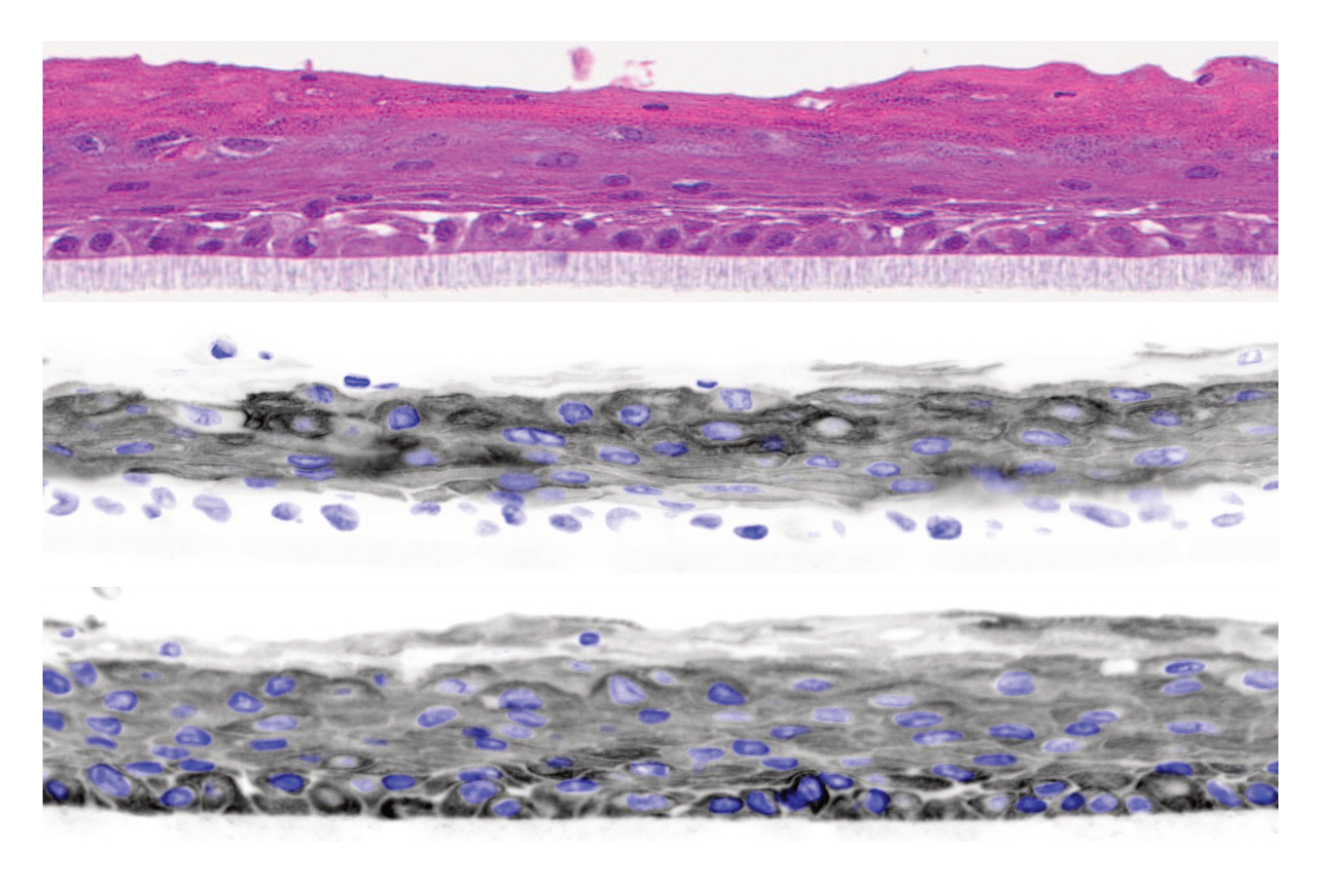

We engineer and utilize human skin equivalent organotypic systems and patient-derived samples to model skin cancer in physiologically relevant contexts. These platforms enable controlled studies of tumor growth, invasion, and microenvironmental interactions.

In particular, we leverage unique systems such as collision tumors to investigate how distinct cell populations interact and contribute to disease. By integrating these models with genomic and single-cell analyses, we gain deeper insight into the biology of rare skin cancers.